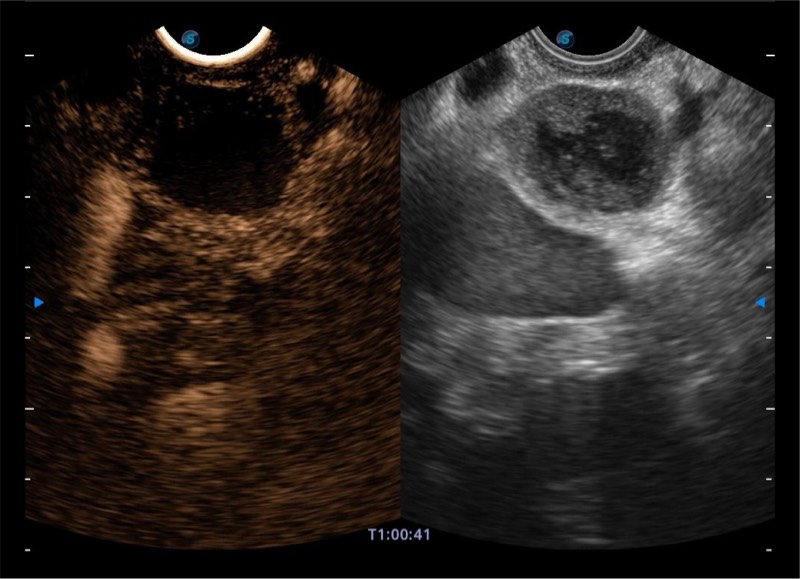

搭载百万级CMOS成像技术

及自主研发凸阵换能器,

可呈现优质的内镜和超声画面

基于二十年的超声技术积累,狗万官方网站提供了最新一代的独立超声主机,在提供高质量图像的同时满足多学科使用。具备常见多普勒技术并提供弹性成像、声学造影等高端影像技术。新一代传感器具有更强的抗干扰能力并减少图像伪影。

4-12MHZ宽频输出